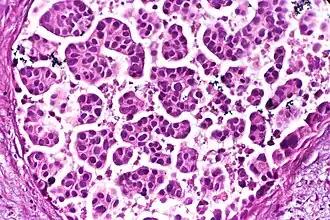

There is also the option to make a "touch prep", wherein a glass slide is simply pressed against the tissue and then exposed to a fixative solution. The glass slide can then be stained and examined. This is feasible for an initial evaluation of suspected lymphomas.

An initial evaluation of a suspected lymphoma is to make a "touch prep" wherein a glass slide is lightly pressed against excised lymphoid tissue, and subsequently stained (usually H&E stain) for evaluation under light microscopy. The second method of histology processing is called frozen section processing. This is a highly technical scientific method performed by a trained histoscientist. In this method, the tissue is frozen and sliced thinly using a microtome mounted in a below-freezing refrigeration device called the cryostat. The thin frozen sections are mounted on a glass slide, fixed immediately & briefly in liquid fixative, and stained using the similar staining techniques as traditional wax embedded sections. The advantages of this method is rapid processing time, less equipment requirement, and less need for ventilation in the laboratory. The disadvantage is the poor quality of the final slide. It is used in intra-operative pathology for determinations that might help in choosing the next step in surgery during that surgical session (for example, to preliminarily determine clearness of the resection margin of a tumor during surgery).